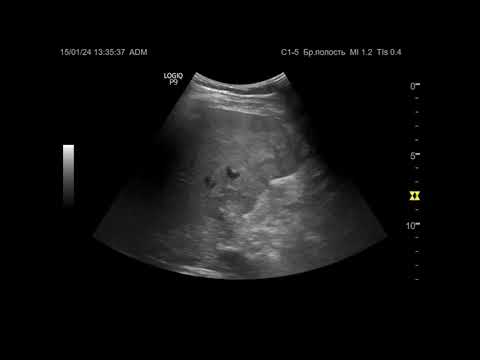

Ультразвуковая диагностика (УЗИ). Доктор Иогансен. Видеопримеры. Выпуск 86. Опухоль печени (4).